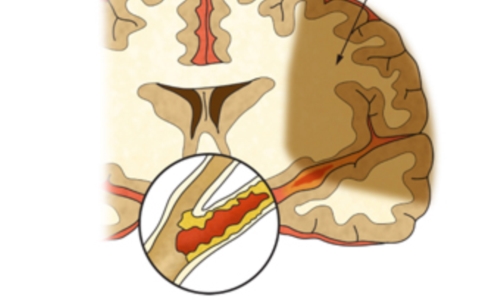

뇌경색 원인은 동맥경화증으로 시작합니다. 병이 든 혈관 어떤 곳에든 핏덩어리가 생겨나면 심장에서 뇌로 흐르는 혈액의 흐름을 방해하게 됩니다. 만약 핏덩어리가 내경동맥이나 뇌혈관을 막게 되면 치명적인 뇌 손상을 입을 수 있습니다. 이렇듯 갑자기 혈관을 막는 경우도 있으나, 혈전에 의하여 점차 혈관 너비가 좁아지면서 허혈성 뇌졸중이 유발되는 경우도 있습니다.